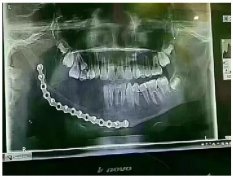

最近一則新聞在朋友圈刷屏:一個 年僅12歲的 小姑娘,因乳牙齲壞太嚴重,引起下頜大面積囊腫,沒辦法只得做了下頜骨切除手術,手術費用花了16萬元,現(xiàn)在恢復的挺好的,只是右邊下邊..[詳細]